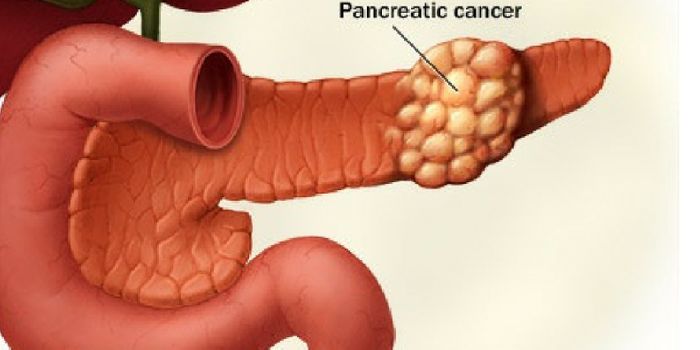

MAR 11, 2016ImmunologyIn 2016, the five-year survival rate for pancreatic cancer increased from seven to eight percent (American Cancer Societ ...

FEB 24, 2017CancerFor years, pancreatic cancer has bested even the most aggressive therapy. But now, Australian researchers report the dis ...

APR 15, 2017CancerTiny non-coding RNA molecules may have a role in the progression of pancreatic cancer, one of the most aggressive diseas ...